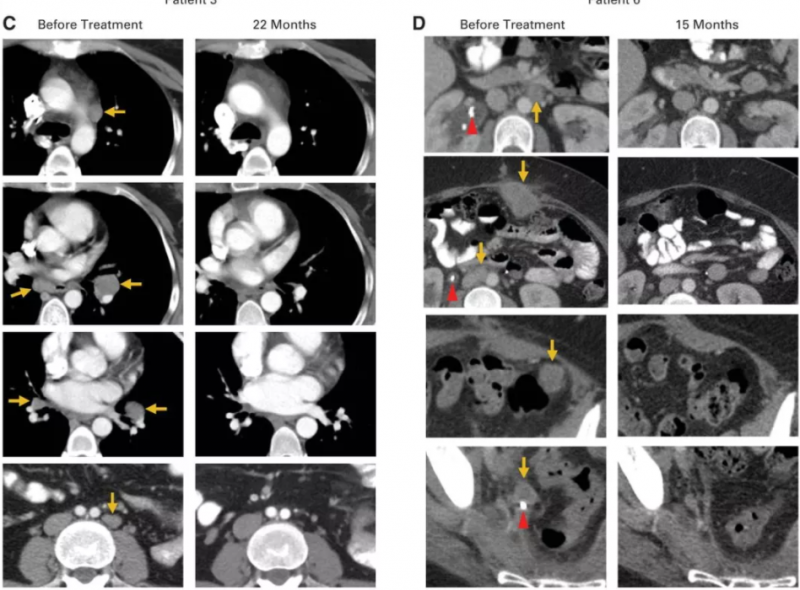

医生对Scott说,即使参加试验她可能也活不到一年,因为她全身至少有七个肿瘤在生长:一个在她的肝脏上,另一个像李子一样大小的肿瘤已经可以直接在肚子上看到,结肠附近有一个肿瘤,另一个已经开始阻塞她的一侧输尿管。

一个月后,她的复查结果显示:肿瘤明显缩小了。特别是腹部凸起的肿瘤已经不见了。Scott激动的哭了,因为她一直不敢触碰那个满是肿瘤的地方,现在它却奇迹般的消失了,就好像从来没出现过一样。

治疗两个月后,Scott的复查结果再次震惊了所有人,包括她自己,影像学检查显示,她的体内已经没有任何癌症的迹象。Scott开心的笑了,又哭了,她觉得这是几年来自己第一次畅快的呼吸。

2015年5月,Hinrichs博士第一次将他参与的这项临床试验的初期结果在肿瘤会议上公布,9名患者中的2名-Scott和Aricca Wallace女士的转移性肿瘤全部消失了,完全缓解时间已超过两年。